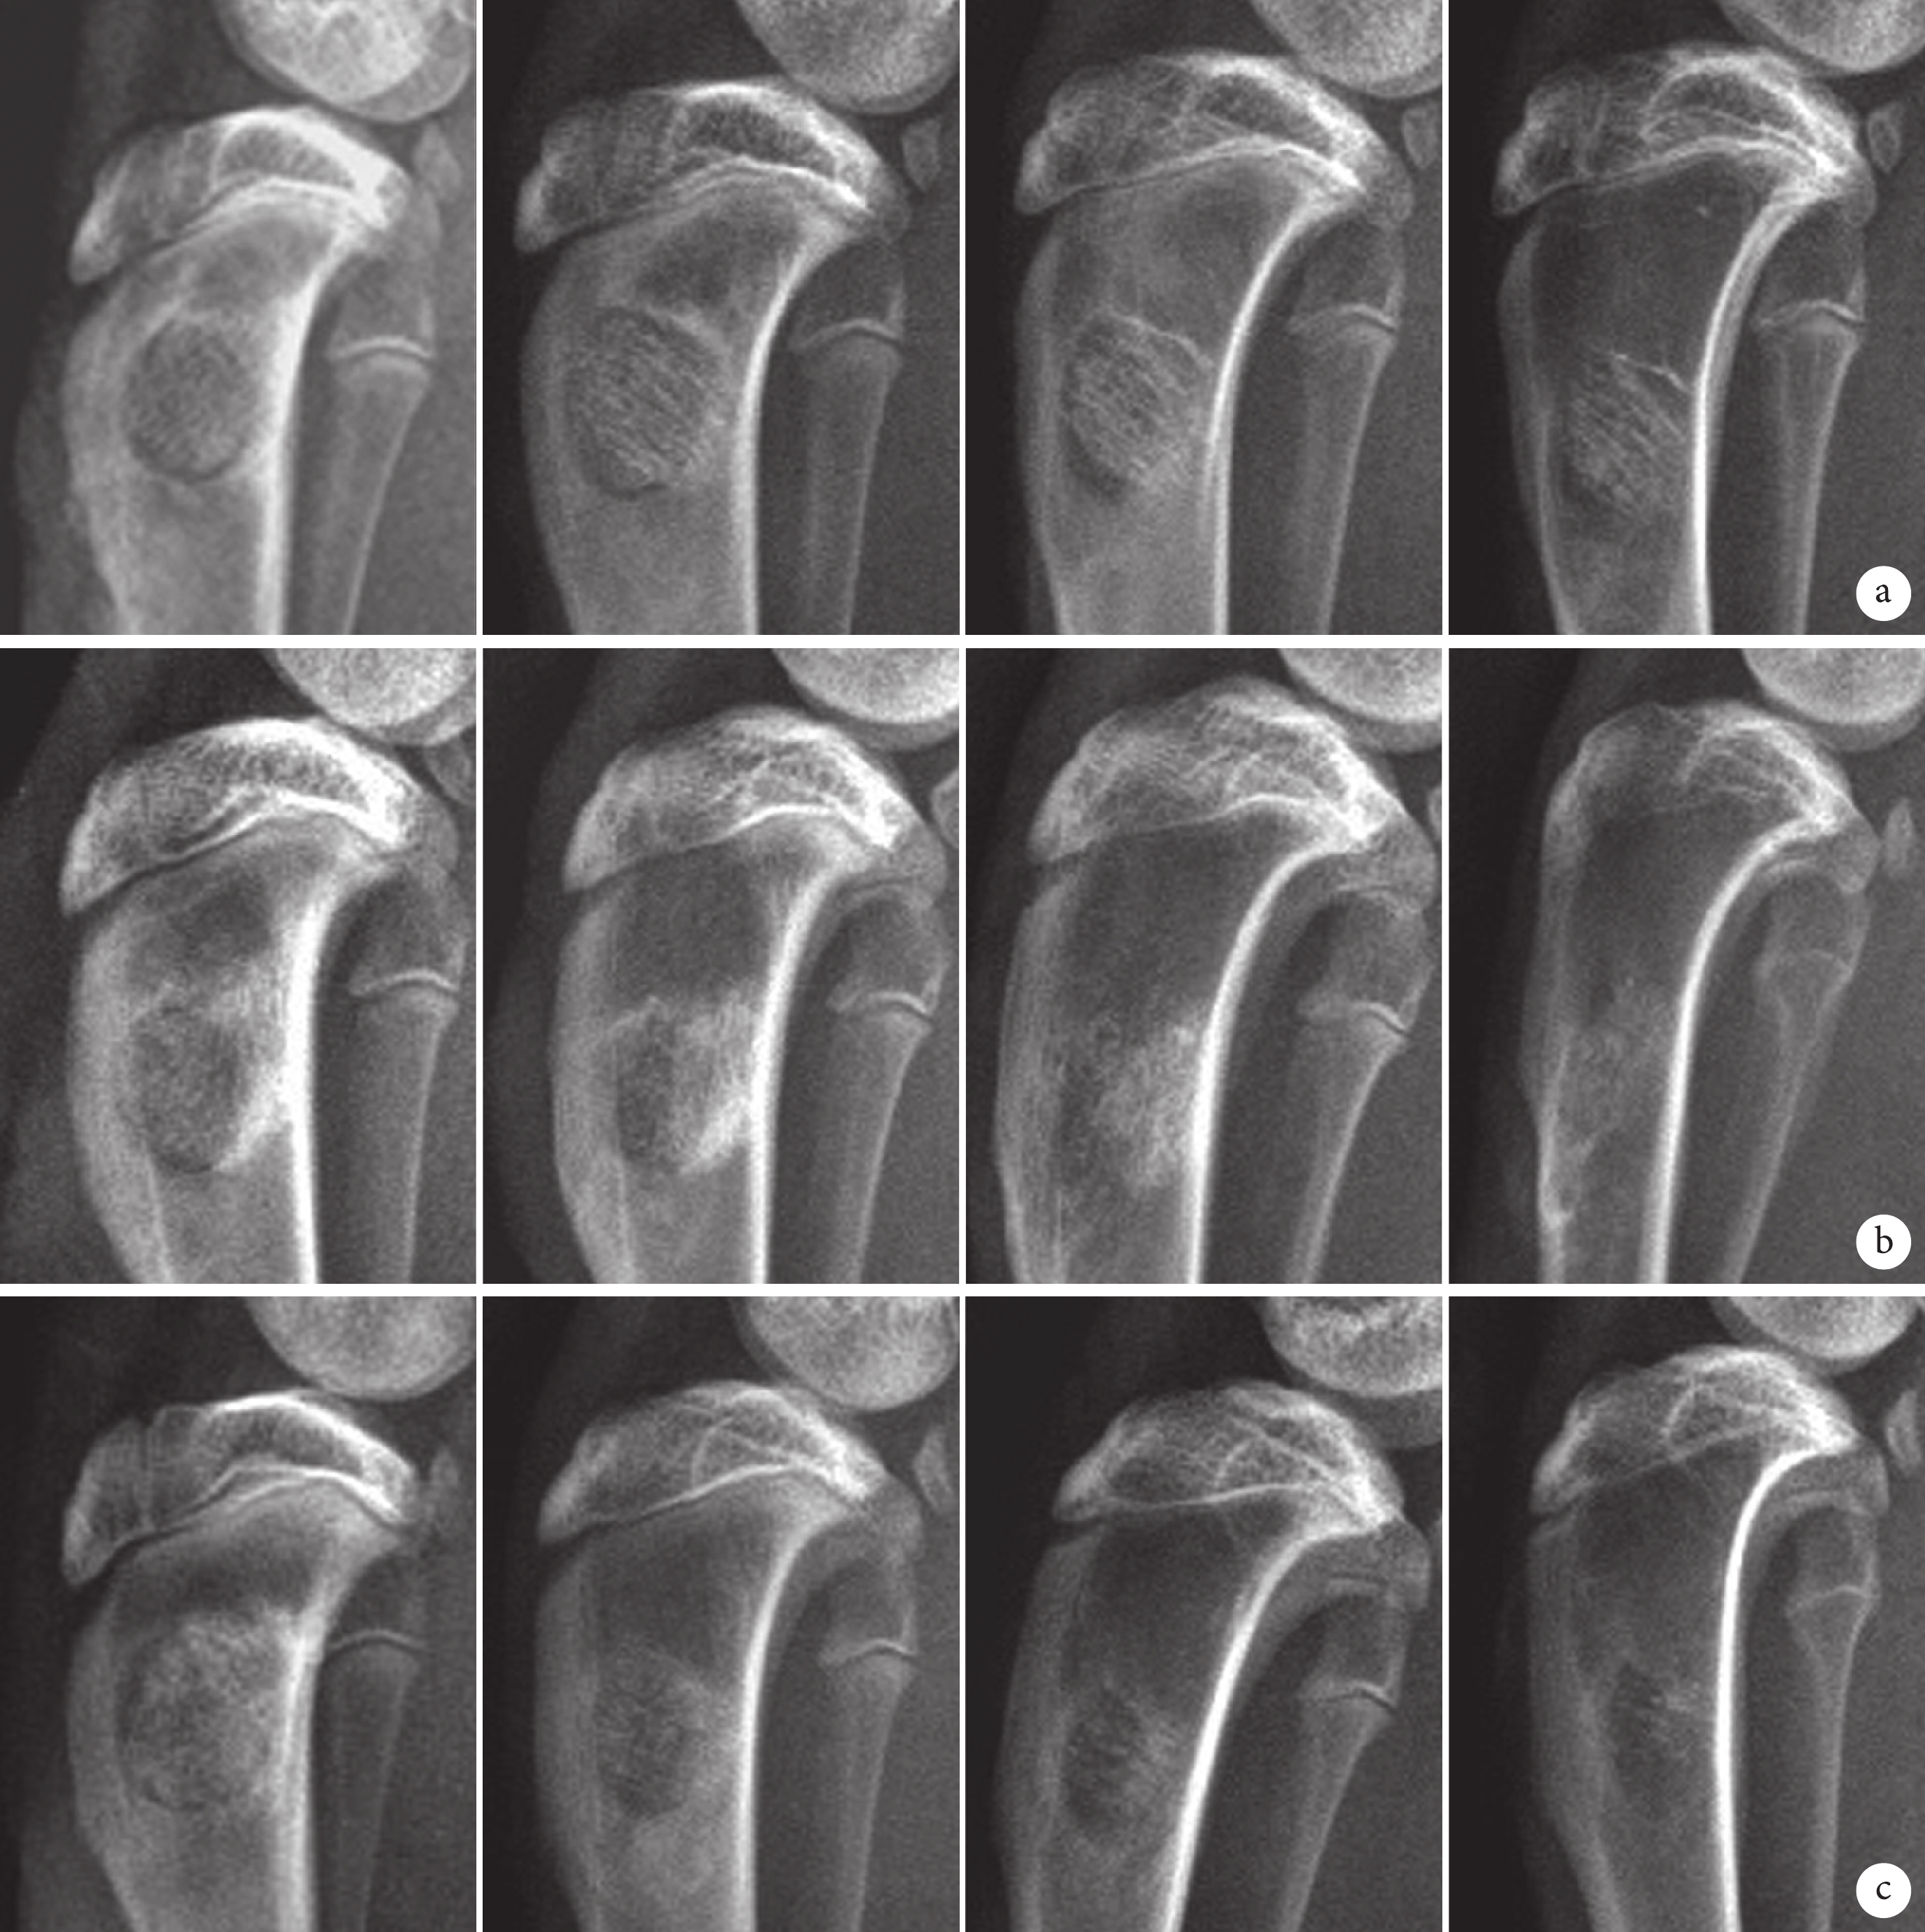

A 組:術后 2 周骨缺損區及支架無明顯變化;4 周時僅少量骨痂形成,骨缺損邊緣仍清晰可見;8 周時骨痂增多,但大部分支架仍存在,無明顯吸收;12 周骨痂進一步增多,但骨缺損區仍以高密度陰影為主,髓腔仍被支架堵塞。B 組:術后 2 周骨缺損區邊緣骨折線稍模糊;4 周時骨缺損區邊緣變模糊,骨痂進一步向支架長入;8 周時新生骨痂明顯增多,且支架大部分吸收,出現部分骨髓腔結構;12 周時骨缺損區新生骨組織形態與正常骨基本相同,新骨塑形好,髓腔再通,骨皮質連續。C 組:術后 2 周骨缺損區及支架無明顯變化;4 周時骨缺損中央區呈低密度組織陰影,可見少量新生骨痂;8 周時骨缺損邊緣模糊,部分骨痂形成;12 周骨缺損區未愈合,支架大部分吸收。見圖 3。

從左至右分別為 2、4、8、12 周 a. A 組;b. B 組;c. C 組

Figure3. X-ray films of 3 groups after operationFrom left to right for 2, 4, 8, and 12 weeks, respectively a. Group A; b. Group B; c. Group C

X 線片評分顯示,除 2 周外,4、8、12 周時 B 組評分均明顯高于 A、C 組,差異有統計學意義(P<0.05)。見圖 4。